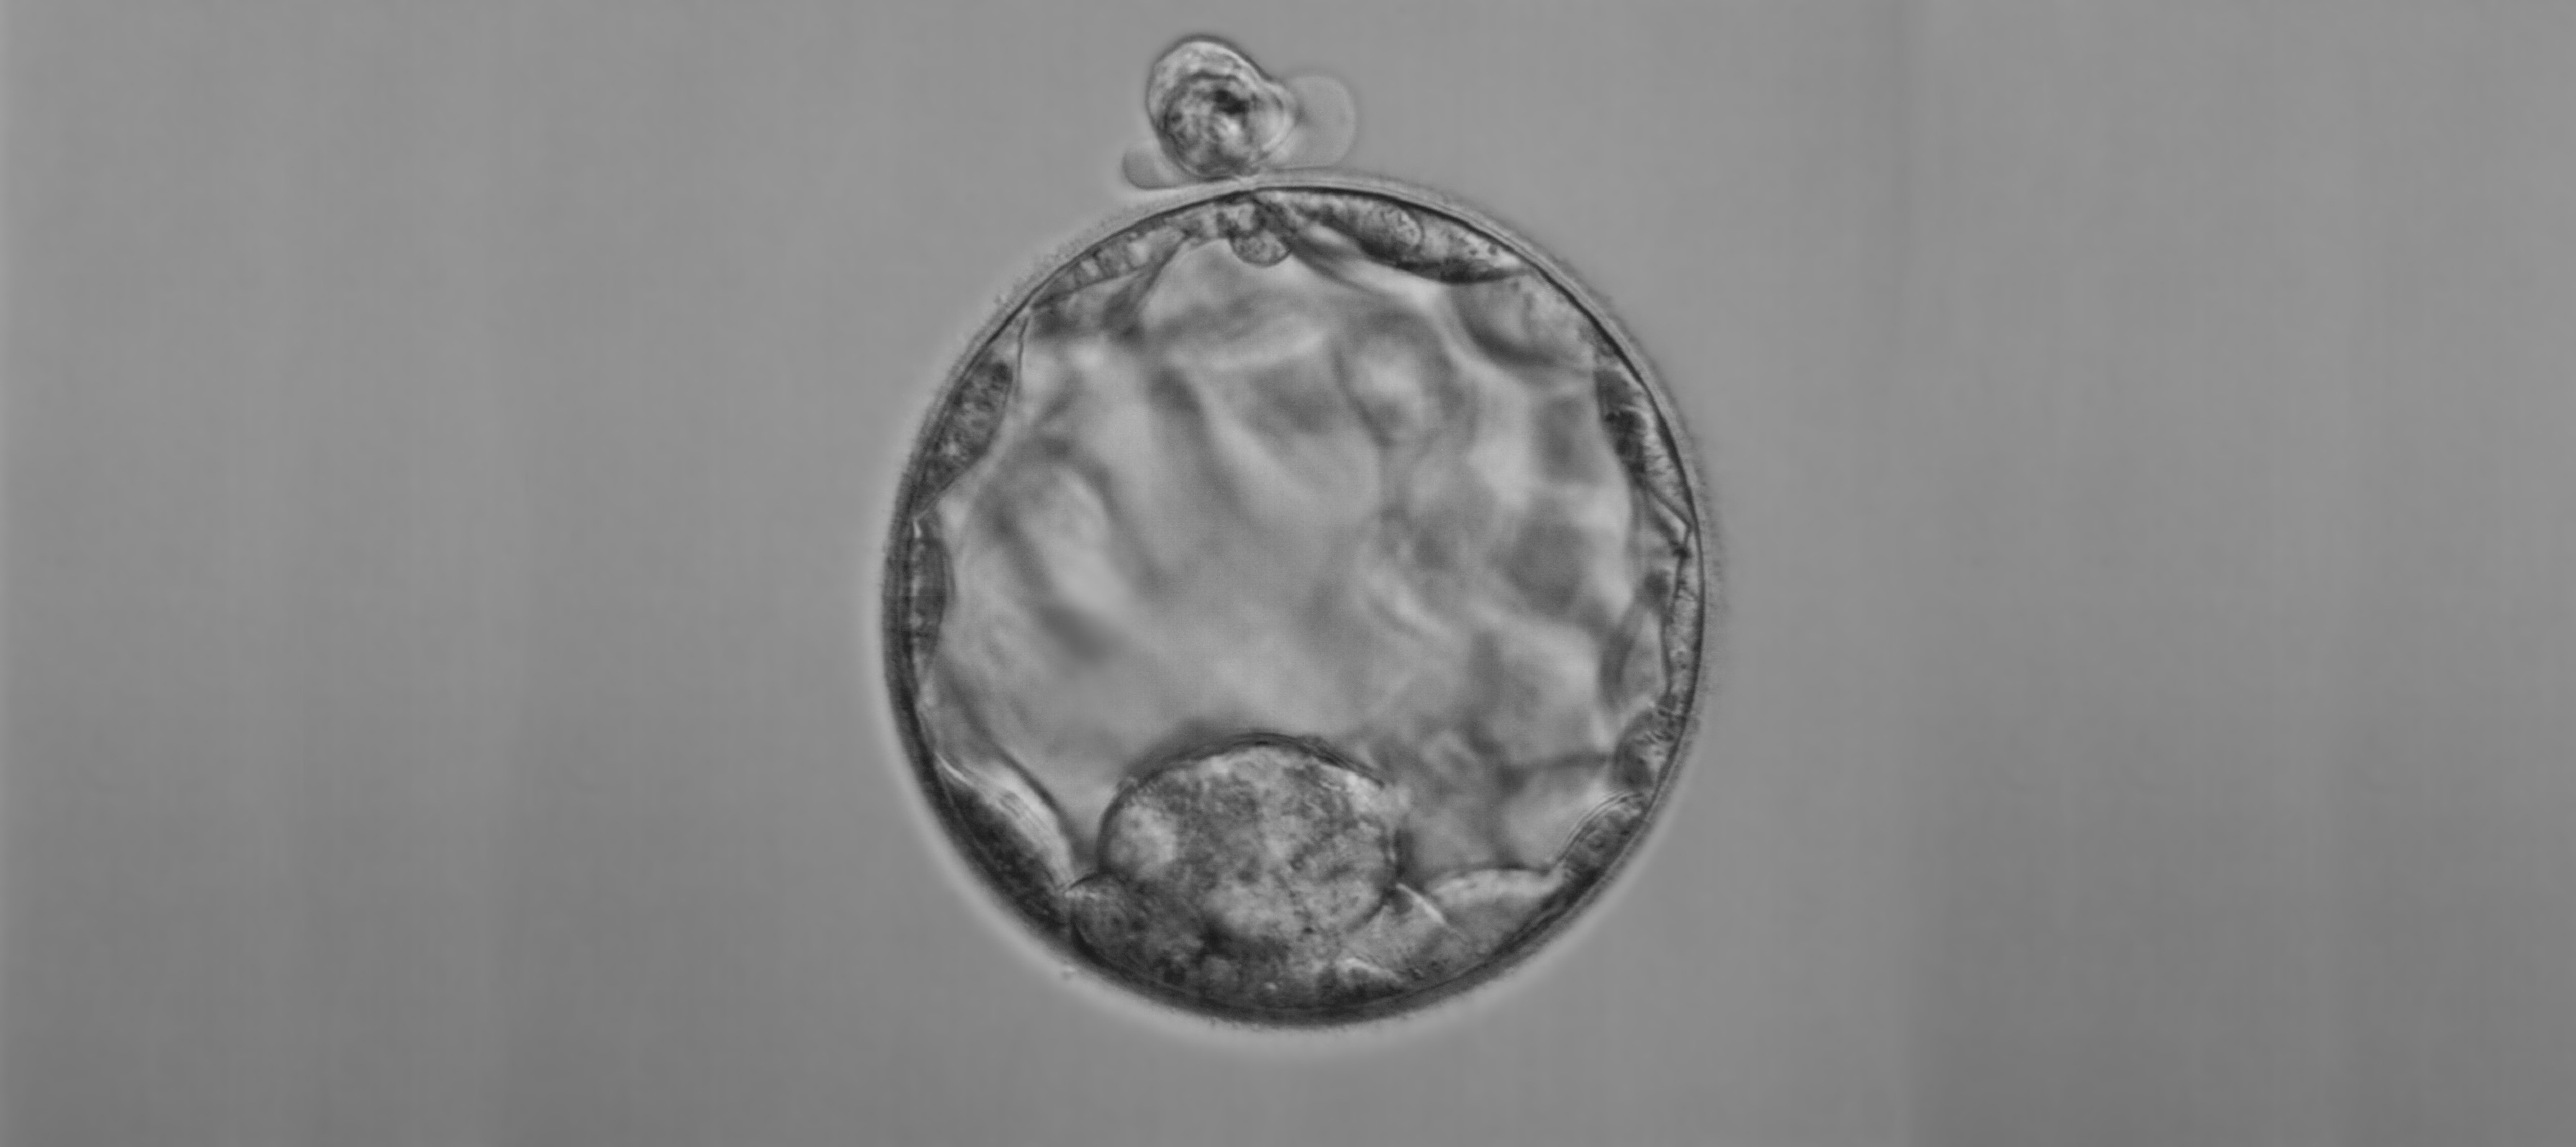

Die Präimplantationsdiagnostik, kurz PID, nutzt verschiedene zellbiologische und molekulargenetische Untersuchungen. Damit können bei durch In-vitro-Fertilisation erzeugten Embryonen Erbkrankheiten oder Veränderungen der Chromosomen erkannt werden. Eltern, die ein hohes Risiko für die Geburt eines Kindes mit einer schweren Erbkrankheit haben, wird es hierdurch ermöglicht, ein Kind zur Welt zu bringen, das von der entsprechenden Krankheit nicht betroffen ist. Seit 2014 ist PID in begrenztem Umfang rechtlich zulässig, nämlich zur Vermeidung schwerer Erbkrankheiten sowie von Tot- und Fehlgeburten aufgrund einer schwerwiegenden Schädigung des Embryos.